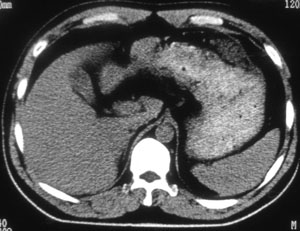

男 46岁 因不明原因低钾数年来院检查,了解有无肾上腺病变。患者补钾后几天又会不明原因缺钾。

患者近几年来明显肥胖,但血压不高。

双侧肾上腺未见明显异常,低钾的原因是否应查一下甲状旁腺功能,或做个颅ct看一下脑内有无多发钙化